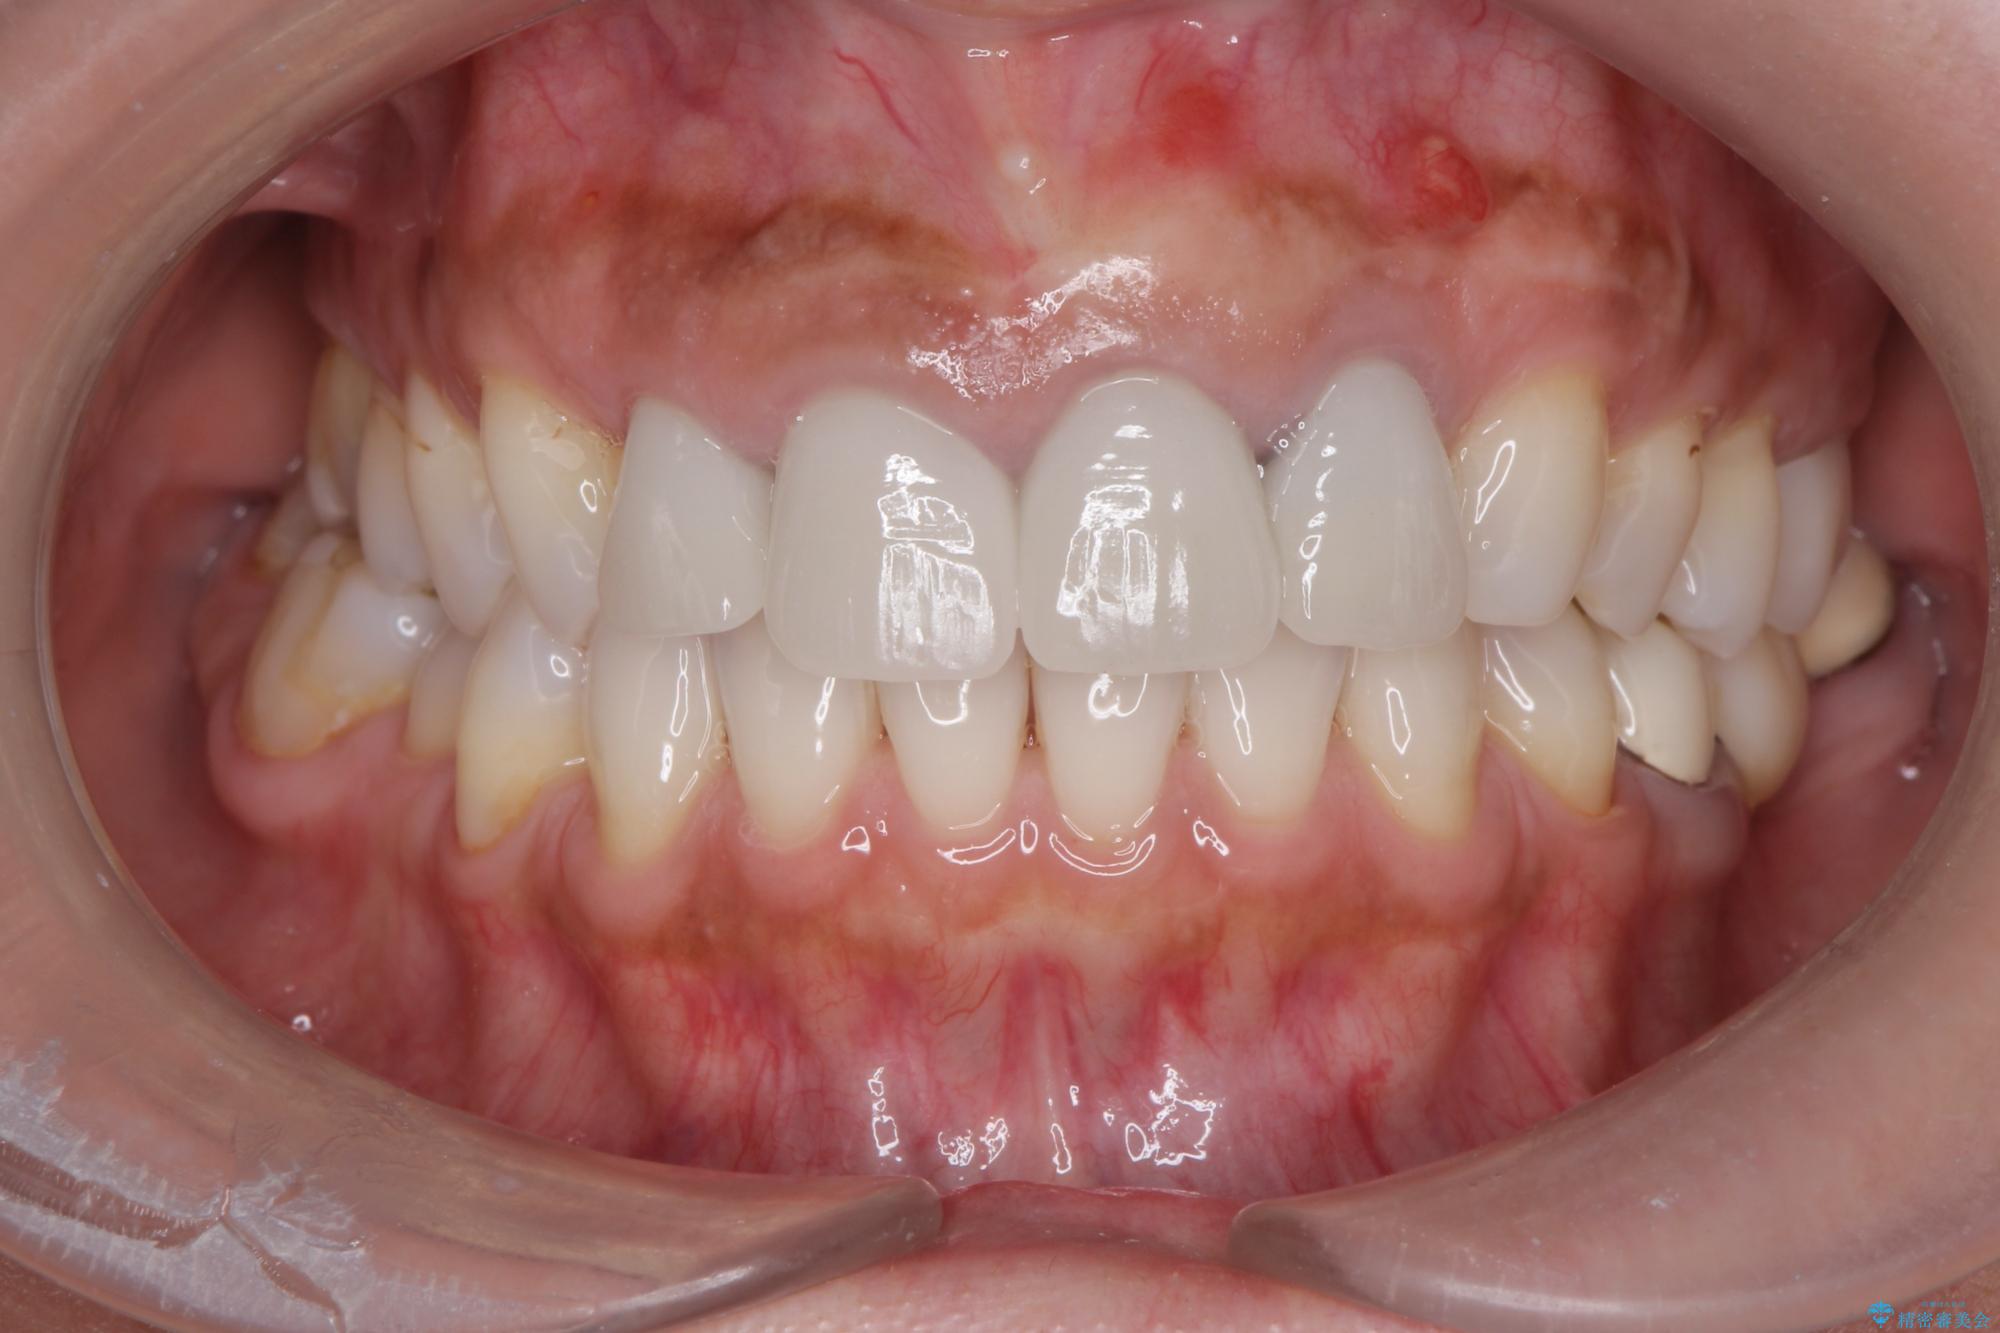

治療後

歯槽堤保存術を併用したブリッジ治療 治療後画像 歯槽堤保存術を併用したブリッジ治療 治療後画像 歯槽堤保存術を併用したブリッジ治療 治療後画像 歯槽堤保存術を併用したブリッジ治療 治療後画像 歯槽堤保存術を併用したブリッジ治療 治療後画像 歯槽堤保存術を併用したブリッジ治療 治療後画像 歯槽堤保存術を併用したブリッジ治療 治療後画像